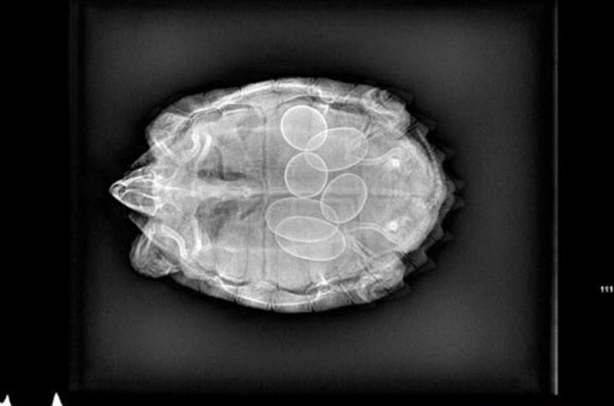

Hamile bir kaplumbağanın röntgen filmi.

Hamile kaplumbağa